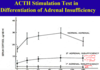

high dose dexamethasone suppression test

cushing’s disease - where is it coming from?

higher dose of dexamethasone will decrease cortisol secretion in normal and patients with pituitary ACTH excess (cushin’g disease) but not in ectopic/adrenal ACTH cushing’s syndrome (there is much more acth in ectopic